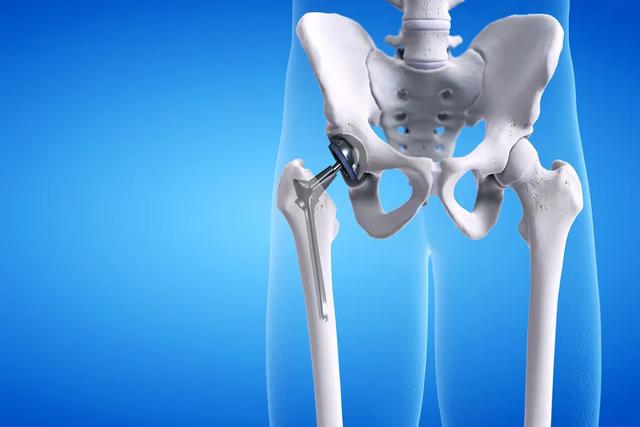

というケースもある。人工股関節置換術の手術患者特に高齢の患者さんの場合、人工関節を骨に固定するために骨セメントを使用する必要があります。骨セメント患者の血圧や心拍数に異常がある場合、人工関節を挿入し、骨セメントを使用する前に、外科医と麻酔医がスタンバイし、常に患者のバイタルサインを監視し、万が一の場合には速やかに蘇生を行うとともに、外科医は人工股関節置換術を行う前に、患者だけでなく家族にもこのような事態が起こりうることを説明する。

- 小遣い骨組織は血行性に富み、特に骨切片、骨髄腔、脊柱管内では、一般に出血量が多く、出血のコントロールが困難である。以下のような侵襲性の高い手技もある。股関節全置換術、脊椎手術、骨盤手術では出血が多くなる.術中の出血量が多い場合、出血性ショックが起こることがある。術中輸血は可能であるが、心肺機能が低下している高齢者にとっては、大量出血は身体的に耐え難いものである。

整形外科の人工股関節置換術はレベル4の手術ですし、脳外科の頭蓋内動脈瘤手術もレベル4の手術ですが、後者は手術部位の違いからリスクも高くなります。 脳は人体の中枢神経系ですから、この部位の手術では脳神経を損傷するリスクが常にあり、そのリスクファクターはかなり高くなります。

例えば、80歳の女性に人工股関節置換術が必要な場合、全身状態、食事、睡眠、便通、精神状態、歩行能力、身の回りのことができるかなどを評価し、補助検査として血液検査、肝腎赤沈、心筋酵素、肺機能、心臓超音波、血管超音波、頭蓋脳CT、胸部CTなどを行い、心肺機能、肝腎機能、深部静脈血栓症の有無、貧血の有無、低蛋白血症の有無などを把握します。手術の禁忌があり、手術のリスクが非常に高い場合は、内科医の指導のもとで病状を調整し、病状が改善するのを待ってから再来院します。本当に手術禁忌があり、手術のリスクが非常に高い場合は、まず内科医の指導のもとで病状を調整し、病状が改善するのを待ってから、手術のリスクを評価するために再来院します。